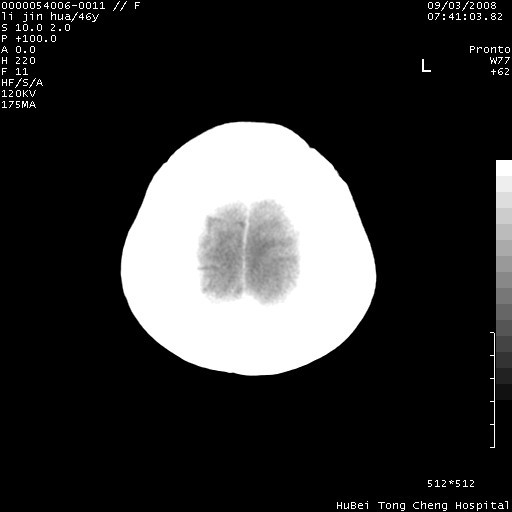

以下是引用panyishengct在2008-9-6 1:47:00的发言:[br]病史?[br]左侧枕/顶叶见一等/低混杂密度占位,壁完整,厚薄较均匀,其前方似有一类似小病灶,周围有水肿带,请结合病史考虑,脓肿可能,不排外转移瘤或胶质瘤,建议增强扫描。